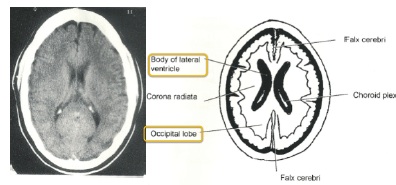

worms = lateral ventricles